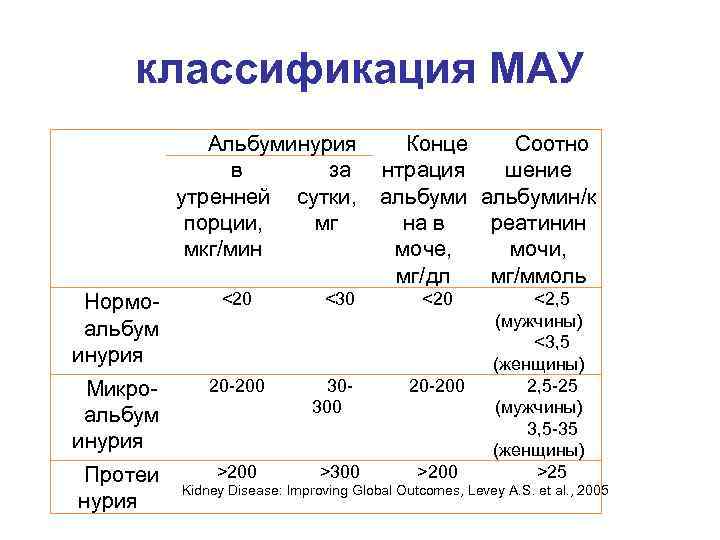

классификация МАУ Альбуминурия в за утренней сутки, порции, мг мкг/мин Нормоальбум инурия <20 Микроальбум инурия 20 -200 Протеи нурия >200 <30 30300 >300 Конце Соотно нтрация шение альбумин/к на в реатинин моче, мочи, мг/дл мг/ммоль <20 20 -200 >200 <2, 5 (мужчины) <3, 5 (женщины) 2, 5 -25 (мужчины) 3, 5 -35 (женщины) >25 Kidney Disease: Improving Global Outcomes, Levey A. S. et al. , 2005

классификация МАУ Альбуминурия в за утренней сутки, порции, мг мкг/мин Нормоальбум инурия <20 Микроальбум инурия 20 -200 Протеи нурия >200 <30 30300 >300 Конце Соотно нтрация шение альбумин/к на в реатинин моче, мочи, мг/дл мг/ммоль <20 20 -200 >200 <2, 5 (мужчины) <3, 5 (женщины) 2, 5 -25 (мужчины) 3, 5 -35 (женщины) >25 Kidney Disease: Improving Global Outcomes, Levey A. S. et al. , 2005